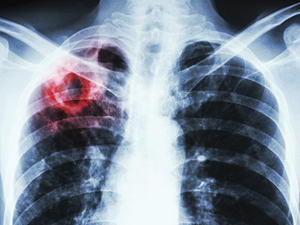

1. Динамічне спостереження за станом здоров’я пацієнтів з діагнозом туберкульоз (ТБ) на амбулаторному етапі.